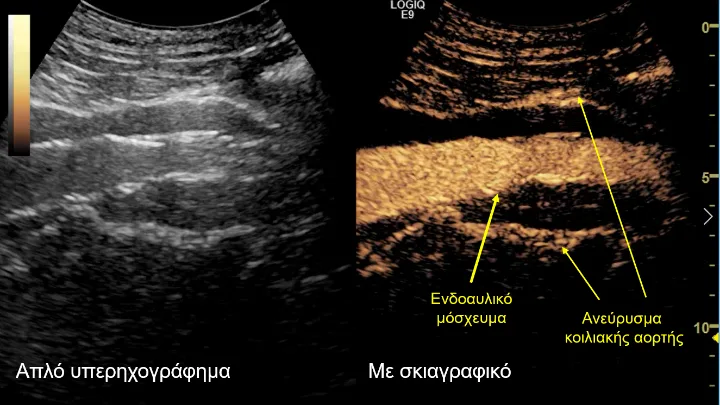

Σε αυτό το πλαίσιο εντάσσεται και ο μετεγχειρητικός υπερηχογραφικός έλεγχος που διεξήχθη στο Τμήμα Υπερήχων από τη δρ Κωνσταντίνα Κυριακοπούλου -MD, PhD, διευθύντρια Τμήματος Υπερήχων, Ιατρικό Κέντρο Αθηνών- και τον Ταξιάρχη Καράμπελα -MD, ακτινολόγο, αναπληρωτή διευθυντή Τμήματος Υπερήχων, Ιατρικό Κέντρο Αθηνών. Το κέντρο αυτό ανήκει στα ελάχιστα ευρωπαϊκά κέντρα, τα οποία ελέγχουν τη βατότητα των σπλαγχνικών αγγείων και την επιτυχή ενδοαγγειακή αποκατάσταση των ανευρυσμάτων υπερηχογραφικά, με τη χρήση ειδικού σκιαγραφικού (SonoVue) που μεταβολίζεται αποκλειστικά στο ήπαρ. Αυτό αποτελεί ιδιαίτερο πλεονέκτημα σε ασθενείς με επηρεασμένη νεφρική λειτουργία.